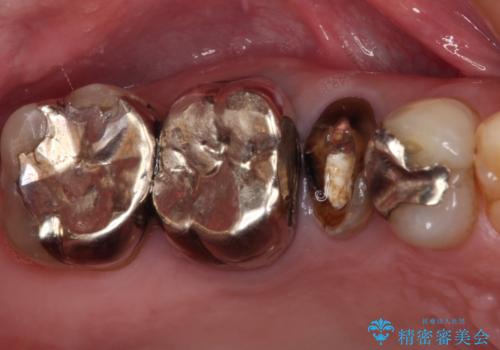

他院で入れた銀歯をやりかえたい。